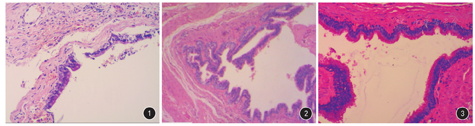

3例患者手术顺利,手术用时分别为75 min、2 h、2 h,出血量为150、100、200 mL。3例患者术后均恢复良好,无相关并发症发生,切口均一期愈合,痊愈出院。(1)患者1术后病理报告:少量肾上腺组织;囊壁组织为纤维结缔组织,其中衬覆纤毛柱状上皮,间有杯状细胞;组织内可见混合腺体、软骨组织;肾上腺皮质增生,支气管源性囊肿(图1)。术后随访12个月,腹部CT检查囊肿无复发。(2)患者2病理报告:囊壁组织为大量纤维结缔组织,内部衬覆假复层纤毛柱状上皮,可见杯状细胞;支气管源性囊肿(图2)。术后随访6个月,腹部CT检查囊肿未见复发。(3)患者3术后病理报告:组织囊壁切缘呈囊性,纤维结缔组织内衬假复层纤毛柱状上皮,上皮内见杯状细胞,上皮下有基底膜,大量炎性细胞浸润,组织中可见少量软骨及肌组织;支气管源性囊肿伴炎症(图3)。术后随访24个月,腹部CT检查囊肿未见复发。